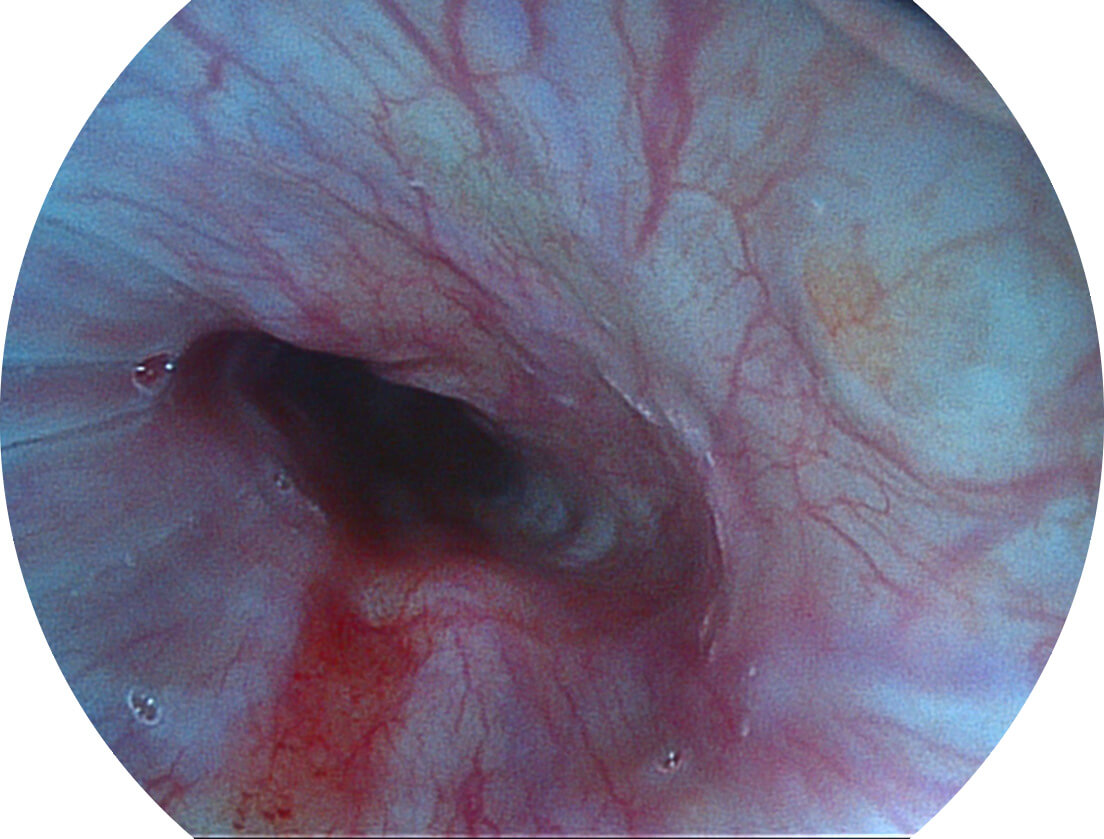

白光图像

VIST图像

强调浅层黏膜结构的同时,保证照明亮度和提升浅层微血管与中层血管颜色对比度,病变边界更清晰。

采用光路合束技术,光谱自由度高,实现了更丰富的照明模式,染色模式SFI及VIST,从远景到近景,助力消化道早期疾病诊断。